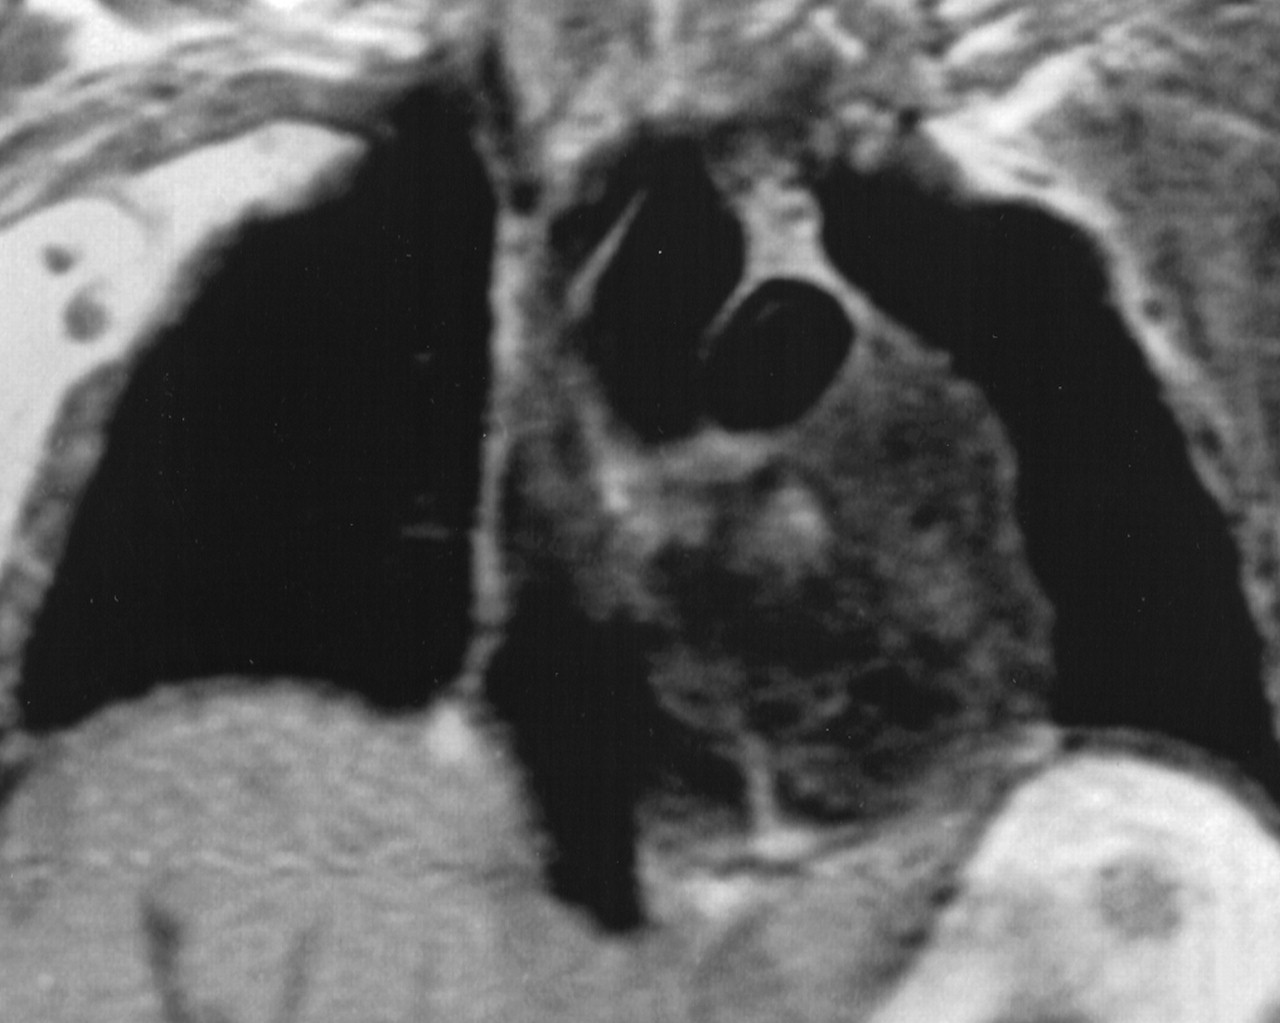

Миксома предсердия

Случай 1: миксома правого предсердия

Случай 2: миома левого предсердия

Случай 3: миксома левого предсердия

Случай 4: миома левого предсердия

Случай 5: миома левого предсердия